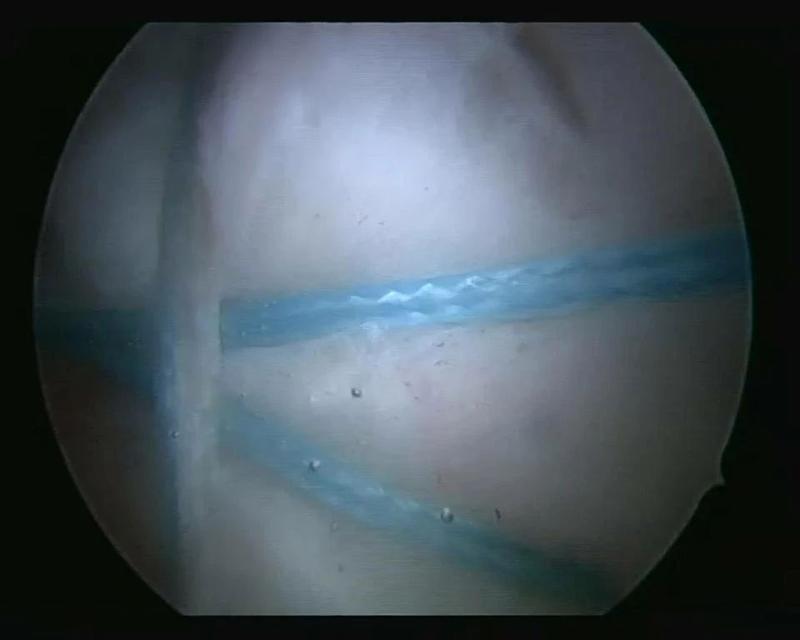

治疗团队完善相关检查后,决定为患者实施巨大肩袖撕裂的全关节镜下修补缝合术。传统的肩关节手术创伤大、出血多、探查不全面、术后恢复慢、有较大手术瘢痕等,通过关节镜对关节内的结构和病变直接观察和治疗,准确性高且损伤性较低。术中治疗团队应用关节镜下微创技术,根据术中实际情况,精准植入缝合锚钉,将撕裂的肩袖缝合回原本的位置,恢复其原本具有的功能。术后患者患肢的活动受限症状立即得到了缓解,患者对治疗效果非常满意,目前恢复良好,右肩活动及功能已有明显改善。